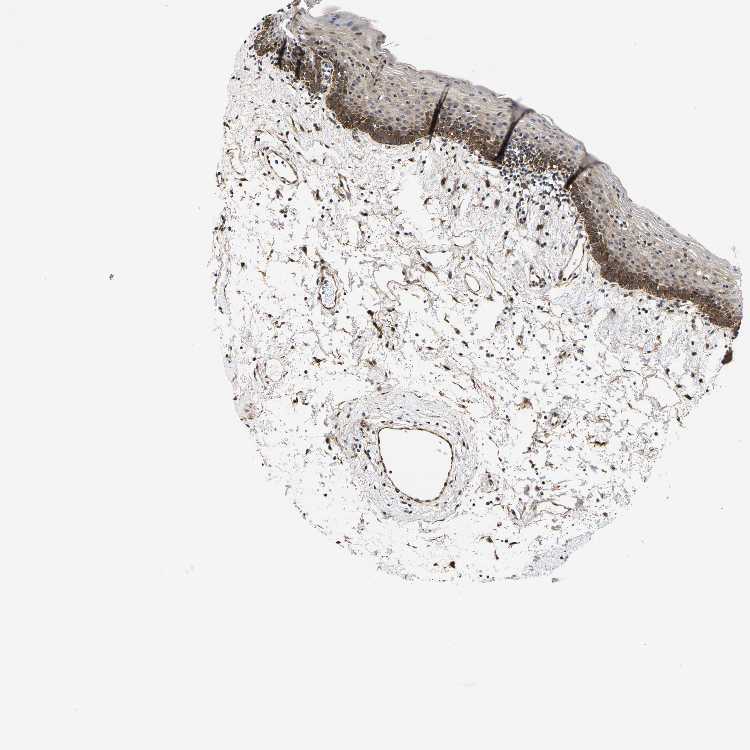

TISSUE PRIMARY DATA ORAL MUCOSA Show tissue menu

ORAL MUCOSA - Antibody stainingi

Antibody staining in the annotated cell types in the current human tissue is reported as not detected, low, medium, or high, based on conventional immunohistochemistry profiling in selected tissues. This score is based on the combination of the staining intensity and fraction of stained cells.

Each image is clickable and will lead to virtual microscopy that enables deeper exploration of all samples and also displays staining intensity scores, fraction scores and subcellular localization as well as patient and tissue information for each sample.

Antibody HPA021076

Squamous epithelial cells High